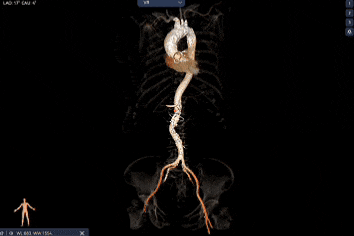

外周双侧入路无明显迂曲、直径可容纳20F大鞘通过,双侧中分叉,穿刺需注意。主动脉弓角弓距可,髂总动脉及分支多处钙化,瓷化升主动脉,钙化由升主动脉蔓延至主动脉弓侧壁及弓顶弓底部,有一定卒中和夹层风险。

经过庄晓东教授团队分析,拟右股动脉作为主入路,使用可调弯长鞘建立通道,使用18mm球囊预扩,选择AV23号Prostyle A®瓣膜进行释放。

Step 1.升主动脉情况评估

过弓示意图